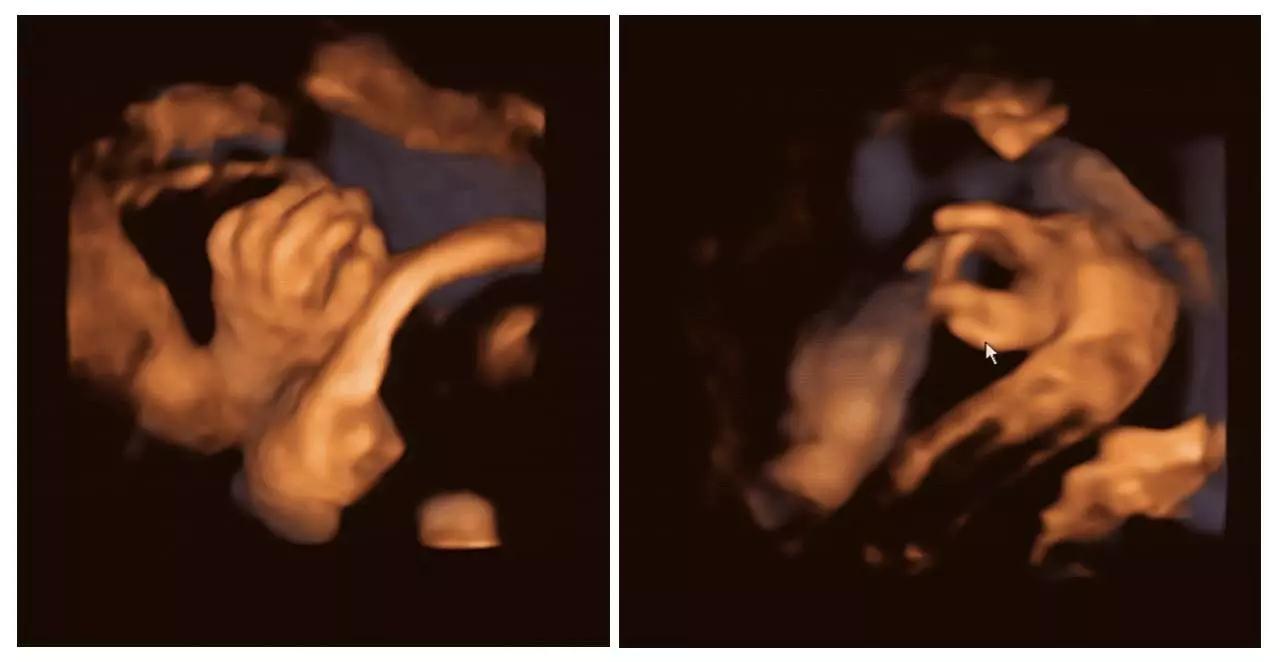

艾玛妇产成功筛查胎儿畸形的案例(部分)——

(右手多指畸形)

正是通过神奇的四维彩超(四维彩超),我们一起见证了这有爱的一幕。四维彩超(四维彩超)的出现对于妇产科学界意义重大,在探头下,我们可以清晰地看见宝宝的动态,看见宝宝发育的情况。不仅如此,四维彩超(四维彩超)能通过清晰的画面对胎儿的体表进行检查,及早发现唇裂、脊柱裂,大脑、肾、心脏、骨骼发育不良等各种畸形情况,检测和发现各种异常。简单的说,四维彩超(四维彩超)的作用,就是从零岁起监测宝宝的发育情况,保障每一个新生儿的健康!